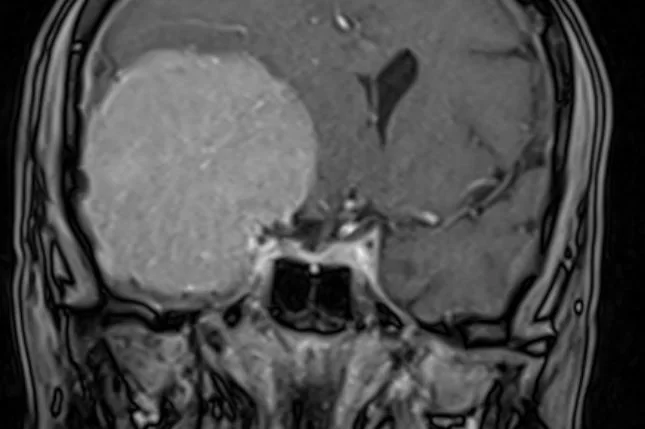

Μηνιγγίωμα: Τύποι, Συμπτώματα, Διάγνωση, Θεραπεία, Κίνδυνος Κακοήθειας και Νέες Εξελίξεις 2026

Αυτό το άρθρο προσφέρει μια ολοκληρωμένη επισκόπηση για τα μηνιγγιώματα, του πιο κοινού πρωτοπαθούς όγκου εγκεφάλου στους ενήλικες. Εξερευνά βασικές πτυχές όπως την προέλευση του …